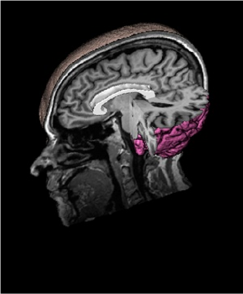

The similarities between fMRI and DTI

modalities include the study of anomaly in WM and

deficits in the size of the corpus callosum (the white

crescent in figure 2.). (Lynn, et al., 2014) have been

supported the hypothesis that the disruption of the

corpus callosum constitutes a major risk factor for

developing autism, resulting in the difficulties that

many autistic people have with words and social

interaction. Unfortunately, to diagnose the

symptoms of autism, the doctor need to do it at least

twice; the first one concerns the observation of

fMRI, the second one the question of how to explain

the observed brain active region in DTI.